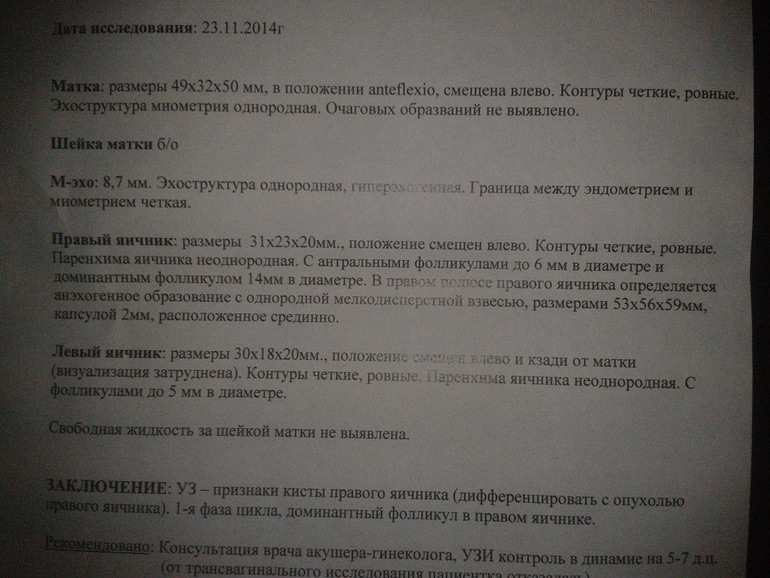

врач не мог рассмотреть левый яичник и так давил, что я чуть глаза наружу... потом аж двумя руками и все таки увидела, что он аж смешено. наверху мочевой пузырь, а вот шарик.... сказала, что киста правого яичника. как приговор для меня! хотя что-то говорила про ЖТ, но как-то не понятно. и очень удивилась, а зачем я БТ меряю.

хотя до этого видела на форуме похожее фото и там у девушки это ЖТ, а вдруг это не оно?